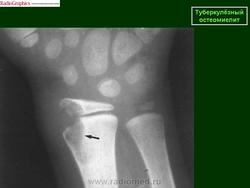

Туберкулез лучезапястного сустава

Эта локализация костно-суставного туберкулеза является одной из редких. Болеют как дети, обычно старше 3-х лет, так и взрослые. Первым клиническим симптомом является слабость в руке, небольшая припухлость мягких тканей. Вскоре появляются боли в области сустава, ограничение движений, атрофия мышц предплечья, образуются натечные абсцессы и свищи. Нередко поражение костей запястья бывает двусторонним или сочетается с поражением других крупных суставов (коленного, локтевого). Туберкулезный остит у детей чаще локализуется в головчатой и крючковидной кости (т. е. в тех костях, в которых раньше появляются ядра окостенения). Первичный очаг может располагаться также в костях проксимального ряда запястья или в лучевой кости, причем у детей нередко в метафизе. При локализации в метафизе лучевой кости первичный очаг переходит сначала на лучелоктевой сустав, а затем на лучезапястный. При рентгенологическом исследовании у детей до 10 лет обращает на себя внимание раннее появление ядер окостенения костей запястья, остеопороз, затем выявляются очаги деструкции костной ткани, которые содержат губчатые секвестры, а также сужение составных щелей между костями запястья и лучезапястного сустава. Постепенно остеопороз нарастает и может захватывать все кости кисти и предплечья. Контуры костей запястья могут быть нечеткими и местами вовсе не дифференцироваться. При локализации первичного очага в метафизе лучевой кости может отмечаться небольшое вздутие кости и периостальные наслоения, которые муфтообразно охватывают метафиз. Затихание процесса клинически характеризуется стиханием воспалительных изменений. При рентгенологическом исследовании появляется четкость контуров очагов деструкции костной ткани, склеротический ободок вокруг них. Остеопороз принимает репаративный характер — редкие костные балки представляются утолщенными и располагаются преимущественно по силовым линиям. Процесс заканчивается фиброзным или костным анкилозом с укорочением запястья. Постартритическая фаза характеризуется анатомо-функциональными изменениями, возможными рецидивами. При рецидивах нарастает остеопороз, контуры очагов деструкции и суставных поверхностей становятся нечеткими, появляются секвестры. Туберкулезное поражение лучезапястного сустава в ряде случаев приходится дифференцировать с неспецифическим остеомиелитом костей предплечья и фиброзной остеодисплазией. В ряде случаев может возникнуть необходимость в дифференциальной диагностике с ревматоидным полиартритом. Однако ревматоидный полиартрит встречается преимущественно у взрослых, характеризуется своеобразными клиническими проявлениями. При рентгенологическом исследовании выявляется преимущественно двустороннее поражение пястно-фаланговых, межзапястных, запястно-пястных, межфаланговых и лучезапястных суставов. На фоне остеопороза в околосуставных отделах выявляются множественные мелкие (2—3 мм) кистоподобные просветления округлой формы и краевые узуры с четкими контурами, окруженные ободком склероза. Секвестры отсутствуют, суставные щели сужены, однако контуры суставных поверхностей хотя и неровные, но четкие. Эти изменения часто ведут к подвывихам и анкилозам. При проведении дифференциальной диагностики необходимо помнить об асептическом некрозе луновидной кости запястья, который встречается у взрослых после однократной травмы или множественых микротравм. При рентгенологическом исследовании луновидная кость уплощена, уплотнена, фрагментирована. Суставные щели не изменены. Остеопороз отсутствует. Свищей и абсцессов не бывает.